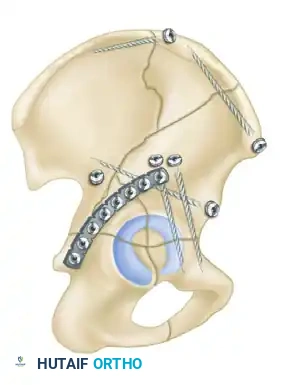

The Ilioinguinal Approach

- Indications: Anterior column, anterior wall, and anterior-dominant both-column fractures.

- Positioning: Supine on a radiolucent table.

- Technique: This is an entirely extrapelvic approach that utilizes three distinct surgical windows to access the anterior column from the SI joint to the pubic symphysis.

- Lateral Window: Between the iliac crest and the iliopsoas muscle.

- Middle Window: Between the iliopsoas/femoral nerve and the external iliac vessels.

- Medial Window: Medial to the external iliac vessels and lateral to the rectus abdominis.

- Biomechanics: This approach allows for the placement of long reconstruction plates along the pelvic brim (iliopectineal line) to buttress the anterior column.